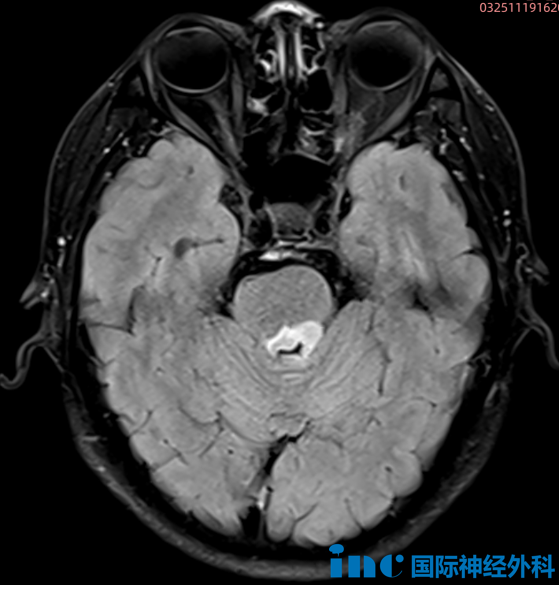

【今日報(bào)道】再闖“生命禁區(qū)”!巴教授一次開顱切除小腦、腦干兩處腦瘤

INC實(shí)時(shí)報(bào)道 一天完成2臺高難度示范手術(shù) 今日,INC巴特朗菲教授主刀、國內(nèi)神經(jīng)外科醫(yī)生團(tuán)隊(duì)全力配合下,突破生命禁區(qū),又完成2臺高難度示范手術(shù)。巴特朗菲教授步履匆匆,往返于蘇州大學(xué)...